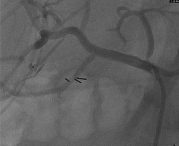

The celiac artery was engaged with a 5F Cobra-1 guide catheter and a 0.014 inch hydrophilic coronary wire was used to cross the lesion (Fig 1).

Crossing a severe stenosis of the celiac trunk from the femoral approach. Note the unfavorable angle of the guide catheter with the target vessel and the ostial location of the lesion.